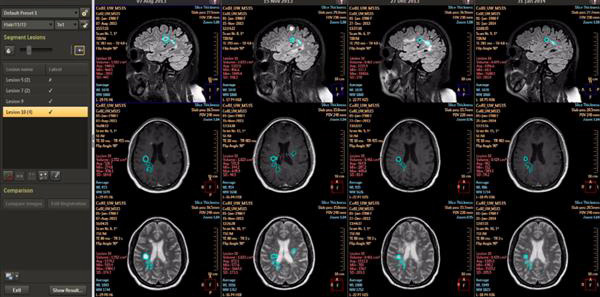

通過新的機器學(xué)習(xí)能力,IntelliSpace Portal 9.0用縱向腦成像(尚未批準(zhǔn)在美國使用)等功能幫助放射科醫(yī)生檢測、診斷疾病并跟進疾病的治療??v向腦成像被用來對神經(jīng)障礙進行縱向評估,這種持續(xù)監(jiān)測功能使得臨床醫(yī)生可以跟蹤疾病的發(fā)展?fàn)顩r。IntelliSpace Portal 9.0上還有CorTech Labs的測量應(yīng)用程序NeuroQuant,臨床醫(yī)生可用它來確定腦體積的損失量。

借助IntelliSpace Portal 9.0,醫(yī)生可更好地研究治療癡呆、中風(fēng)、肌萎縮性脊側(cè)索硬化(ALS)、多發(fā)性硬化(MS)等腦損傷和神經(jīng)性疾病。